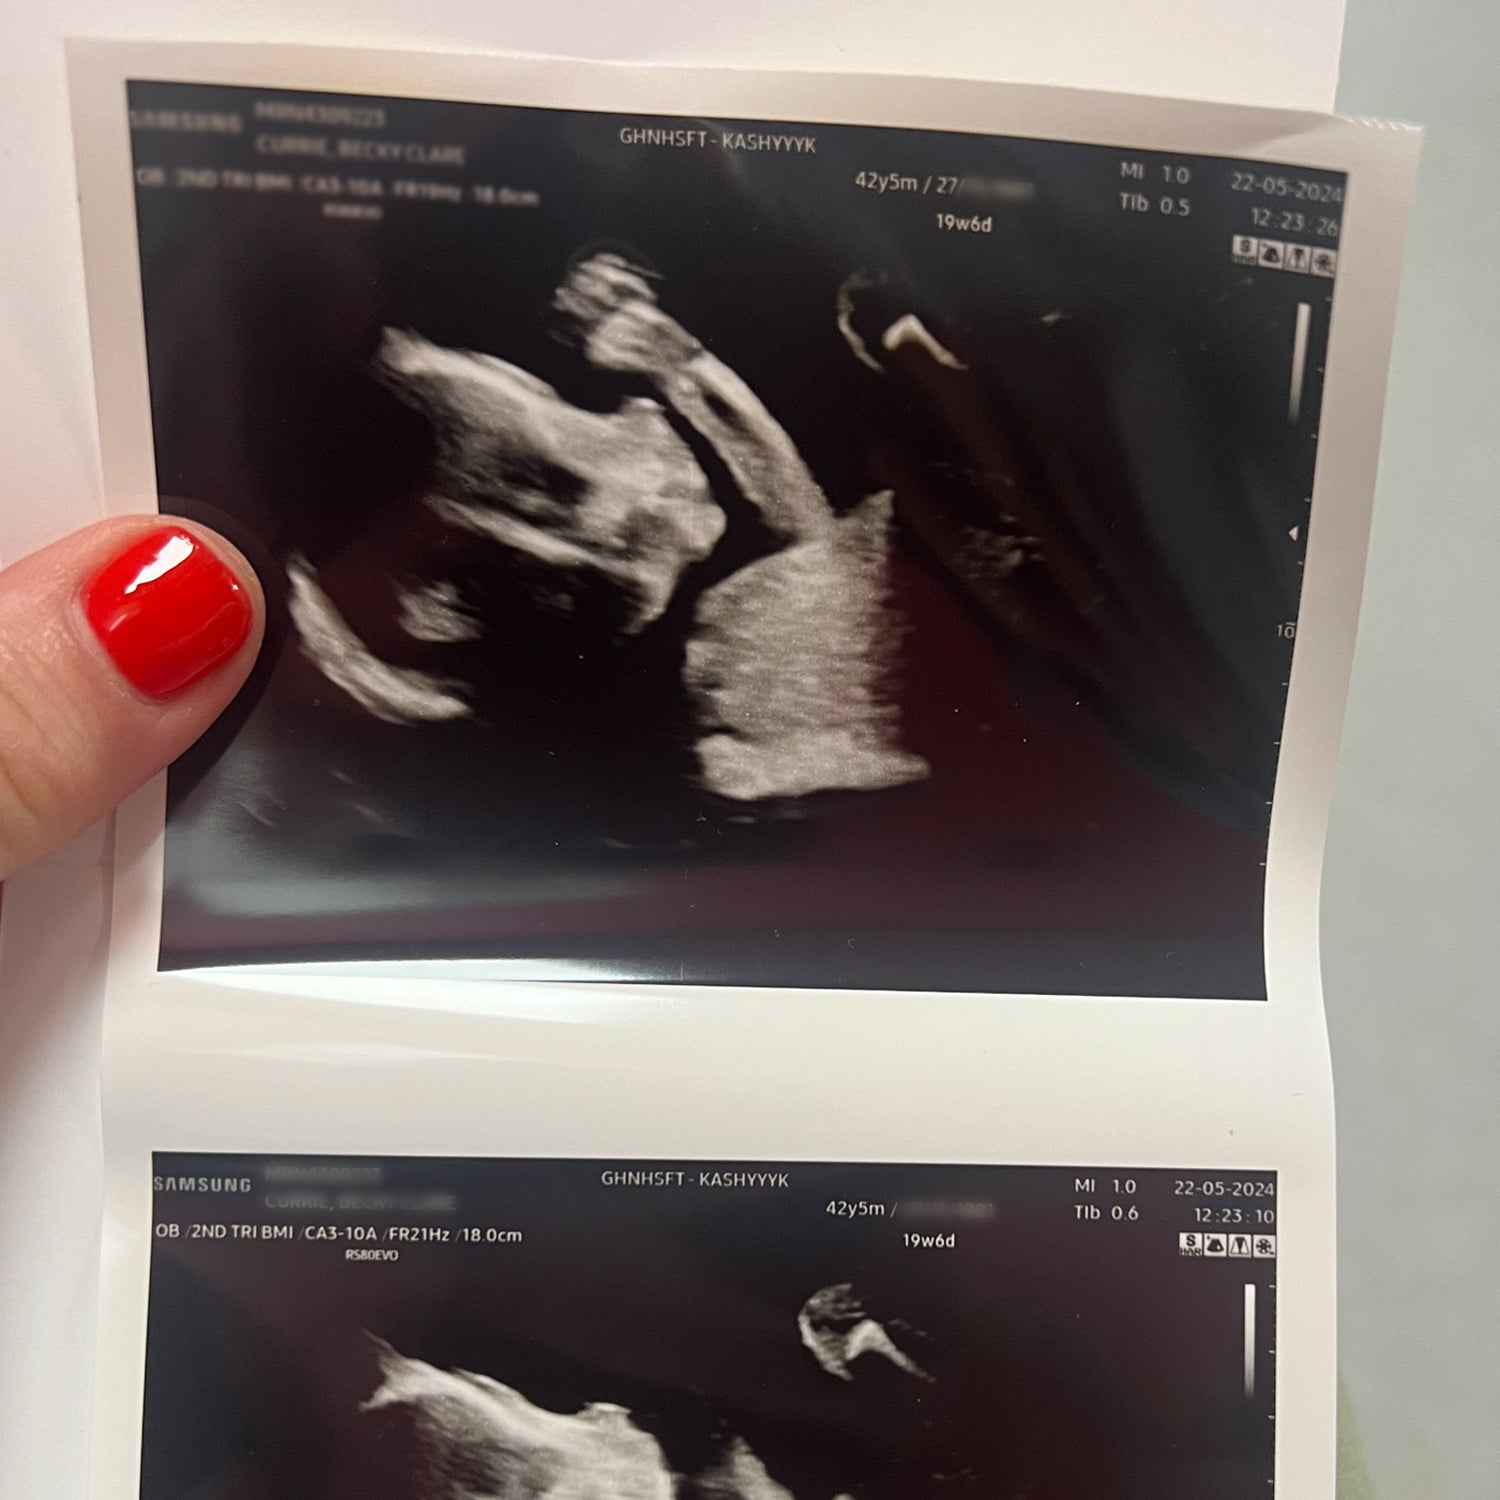

When they finally did test, the results were positive. The joy they experienced was tempered with caution due to past losses, but as they awaited their first scan, the nervous anticipation quickly turned to reassurance when the sonographer found a steady, healthy heartbeat.

Now six months pregnant, Becky and Thomas are thriving. Their story highlights the ongoing importance of wellness and holistic health as they navigate pregnancy with minimal symptoms and steady energy, something they attribute in part to the continued use of Naître’s pregnancy supplements.